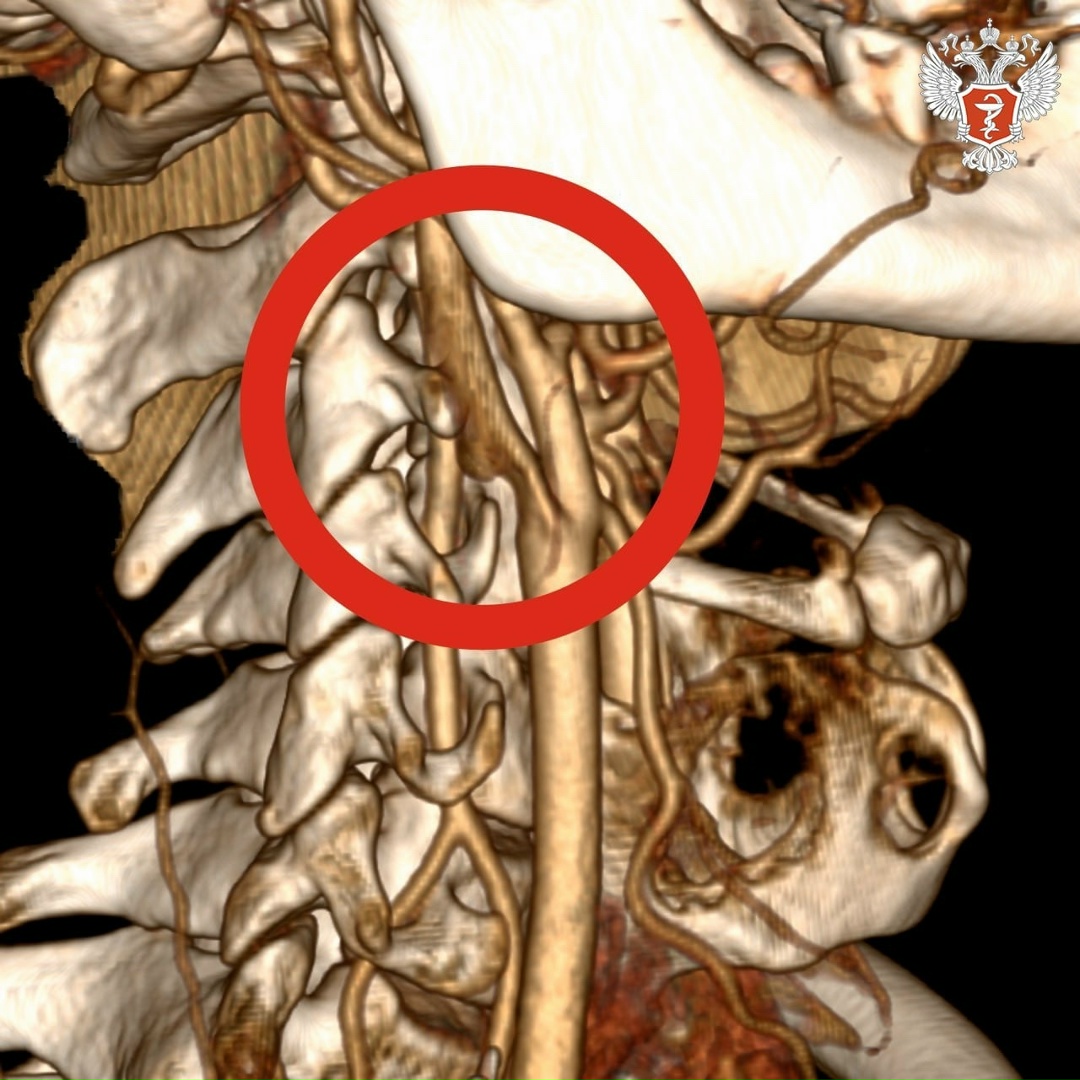

➡️ В ходе исследований врачи выявили тромб длиной около 4 см в просвете правой внутренней сонной артерии. Он нарушал кровоснабжение головного мозга. В любой момент тромб мог оторваться и закрыть магистральные артерии правого полушария, что привело бы к обширному ишемическому инсульту.

Хирурги экстренно провели операцию и удалили тромб, изъязвленную атеросклеротическую бляшку во внутренней и общей сонных артериях и восстановили анатомию сосудов.